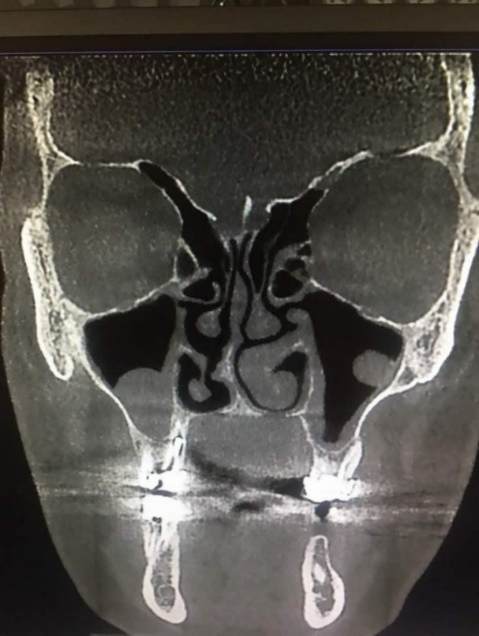

In males, 23.7% of the increase was normal mucosa, 36.84% was sinusitis, and 39.47% was mucositis. In females, 32.43% of the increase was normal, 18.92% was sinusitis, and 48.65% was mucositis (Table 3 and Figure 2).

Figure 2.Spore-shaped septal deviation.